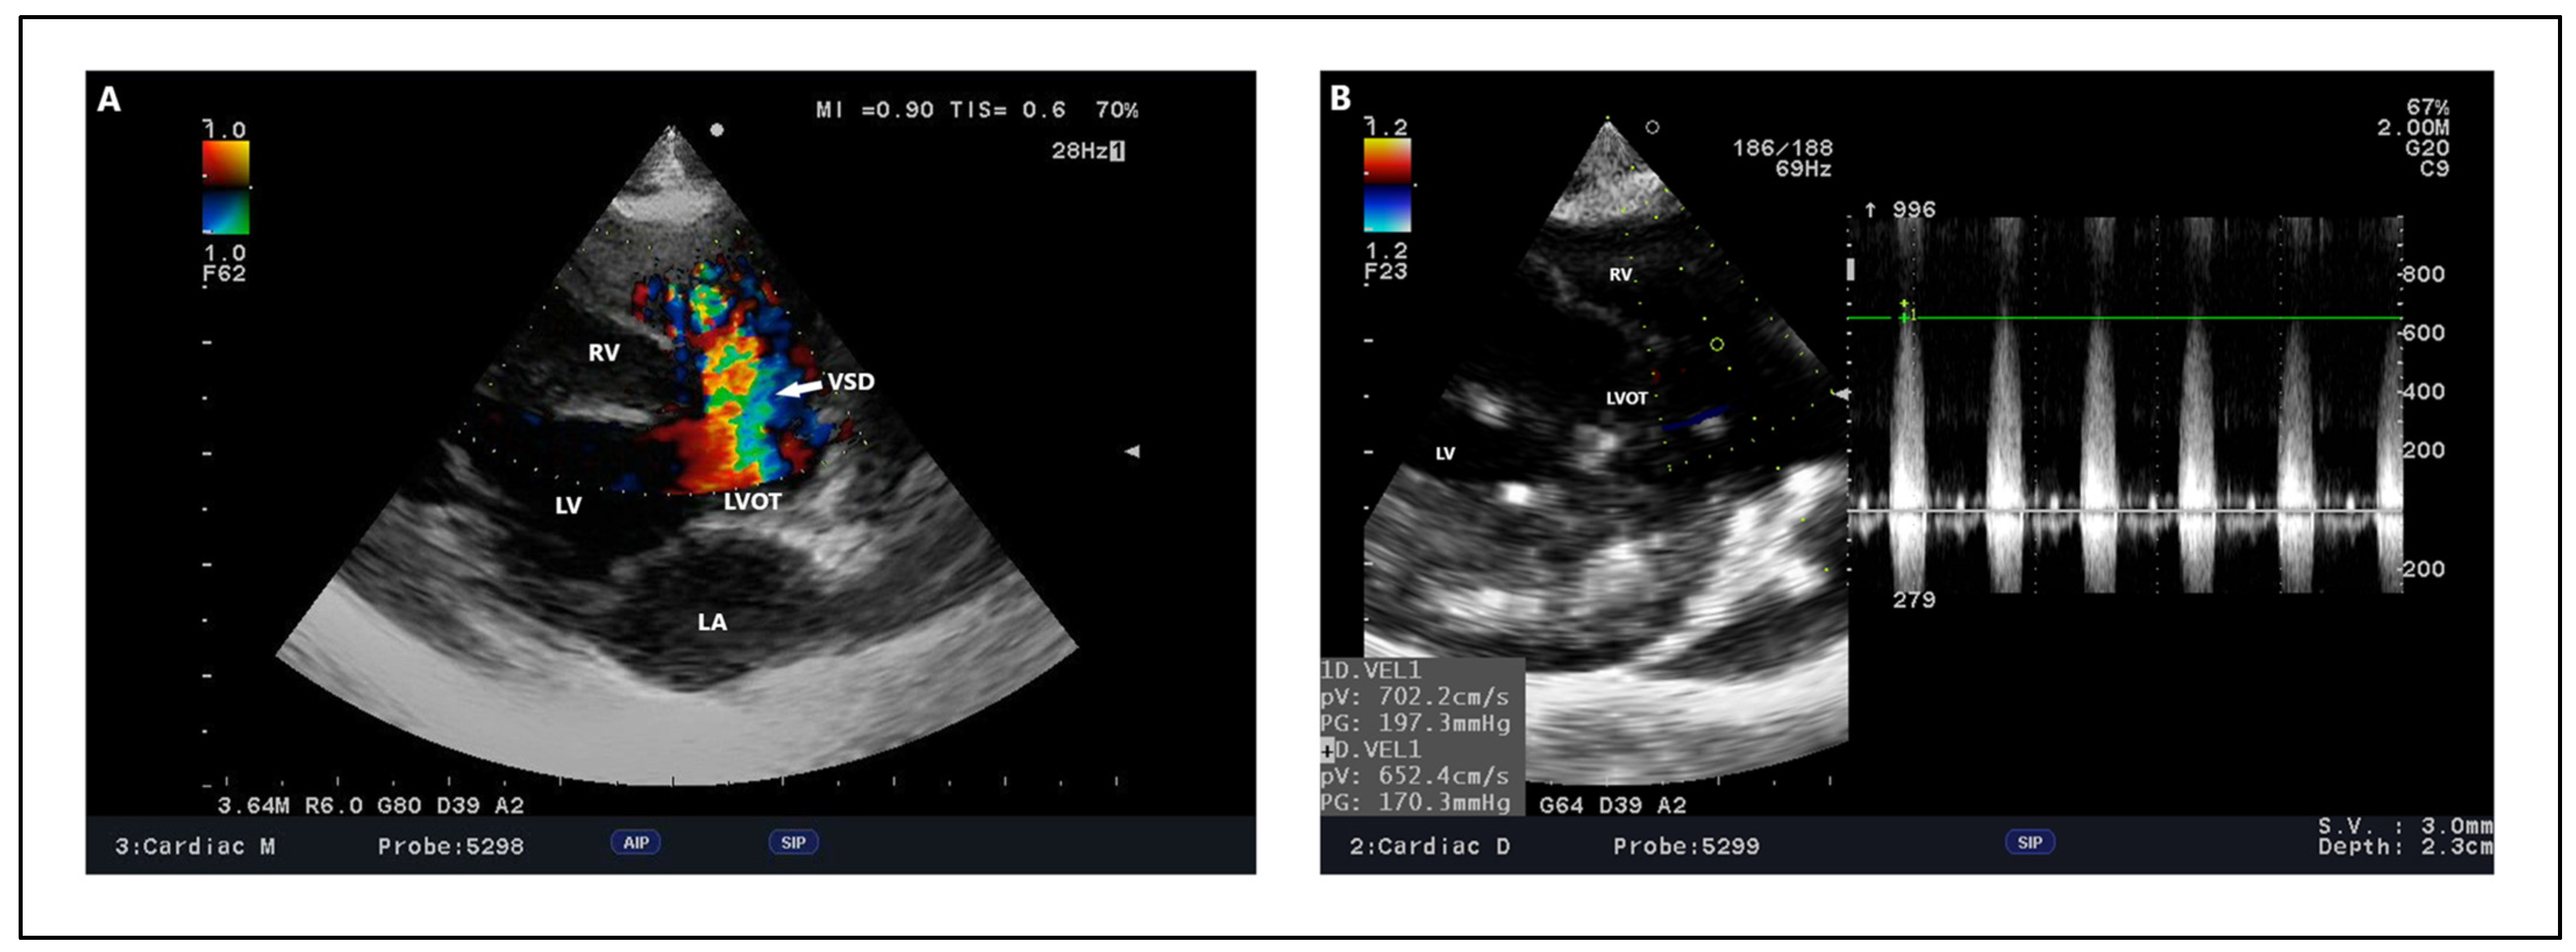

4.2. Echocardiography, Radiography, ECG Findings